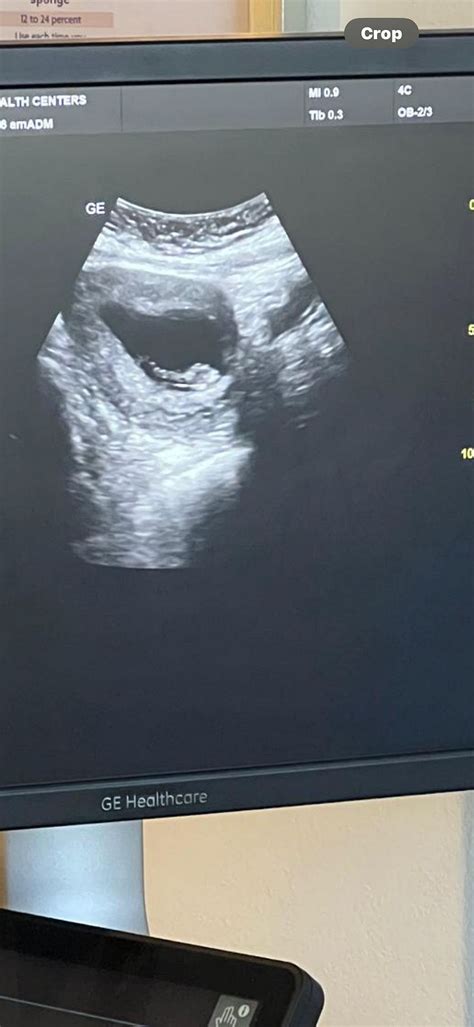

A 9 week ultrasound is a medical imaging procedure that uses high-frequency sound waves to create images of the fetus and the uterus. This non-invasive test is typically performed transabdominally or transvaginally, depending on the preference of the healthcare provider and the position of the uterus. The primary goal of a 9 week ultrasound is to confirm the viability of the pregnancy, assess the fetal heart rate, and measure the size of the fetus.

• Imaging: The ultrasound technician will move the transducer over the abdomen or insert it into the vagina to capture images of the uterus and fetus. The images will be displayed on a monitor, allowing the healthcare provider to assess the fetus's development.

• Measurement: The healthcare provider will measure the size of the fetus, typically focusing on the crown-rump length (CRL), which is the distance from the top of the head to the bottom of the buttocks. This measurement helps determine the gestational age and overall growth of the fetus.

• Fetal Size: The crown-rump length (CRL) is a critical measurement that helps determine the gestational age. At 9 weeks, the CRL is typically around 21-27 mm.

• Gestational Sac: The gestational sac, which contains the fetus and amniotic fluid, should be visible and measure appropriately for the gestational age.

• Heartbeat: The fetal heartbeat should be detectable and within the normal range.